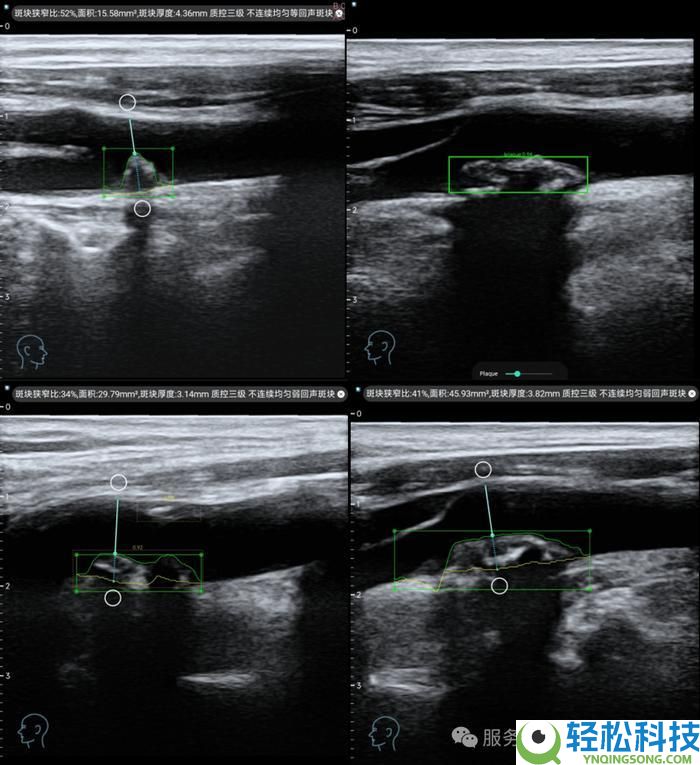

基于深度学习算法,实现对颈动脉超声影像的实时分析,自动完成血管内中膜厚度测量、斑块识别与量化评估,诊断准确率达到三甲医院专家水平。